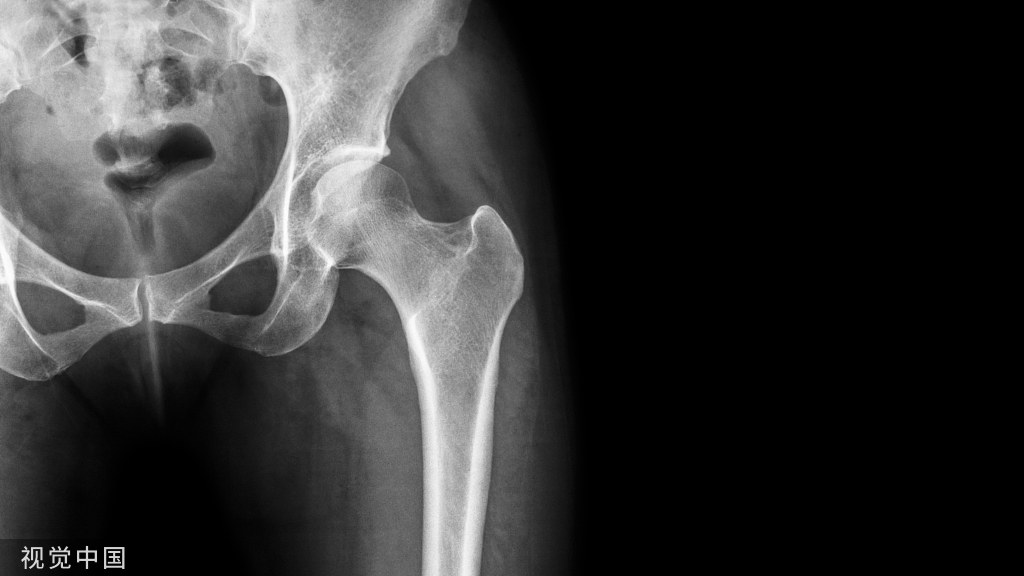

髂腹股沟入路,顺行后柱螺钉是固定后柱的最佳方式,它可经塑形好的钢板置入,也可于钢板外置入。

Via Ilioinguinal approach, antegrade posterior column screws are the optimal implants to stabilize the posterior column, which can be placed either through the contoured plate  or not.